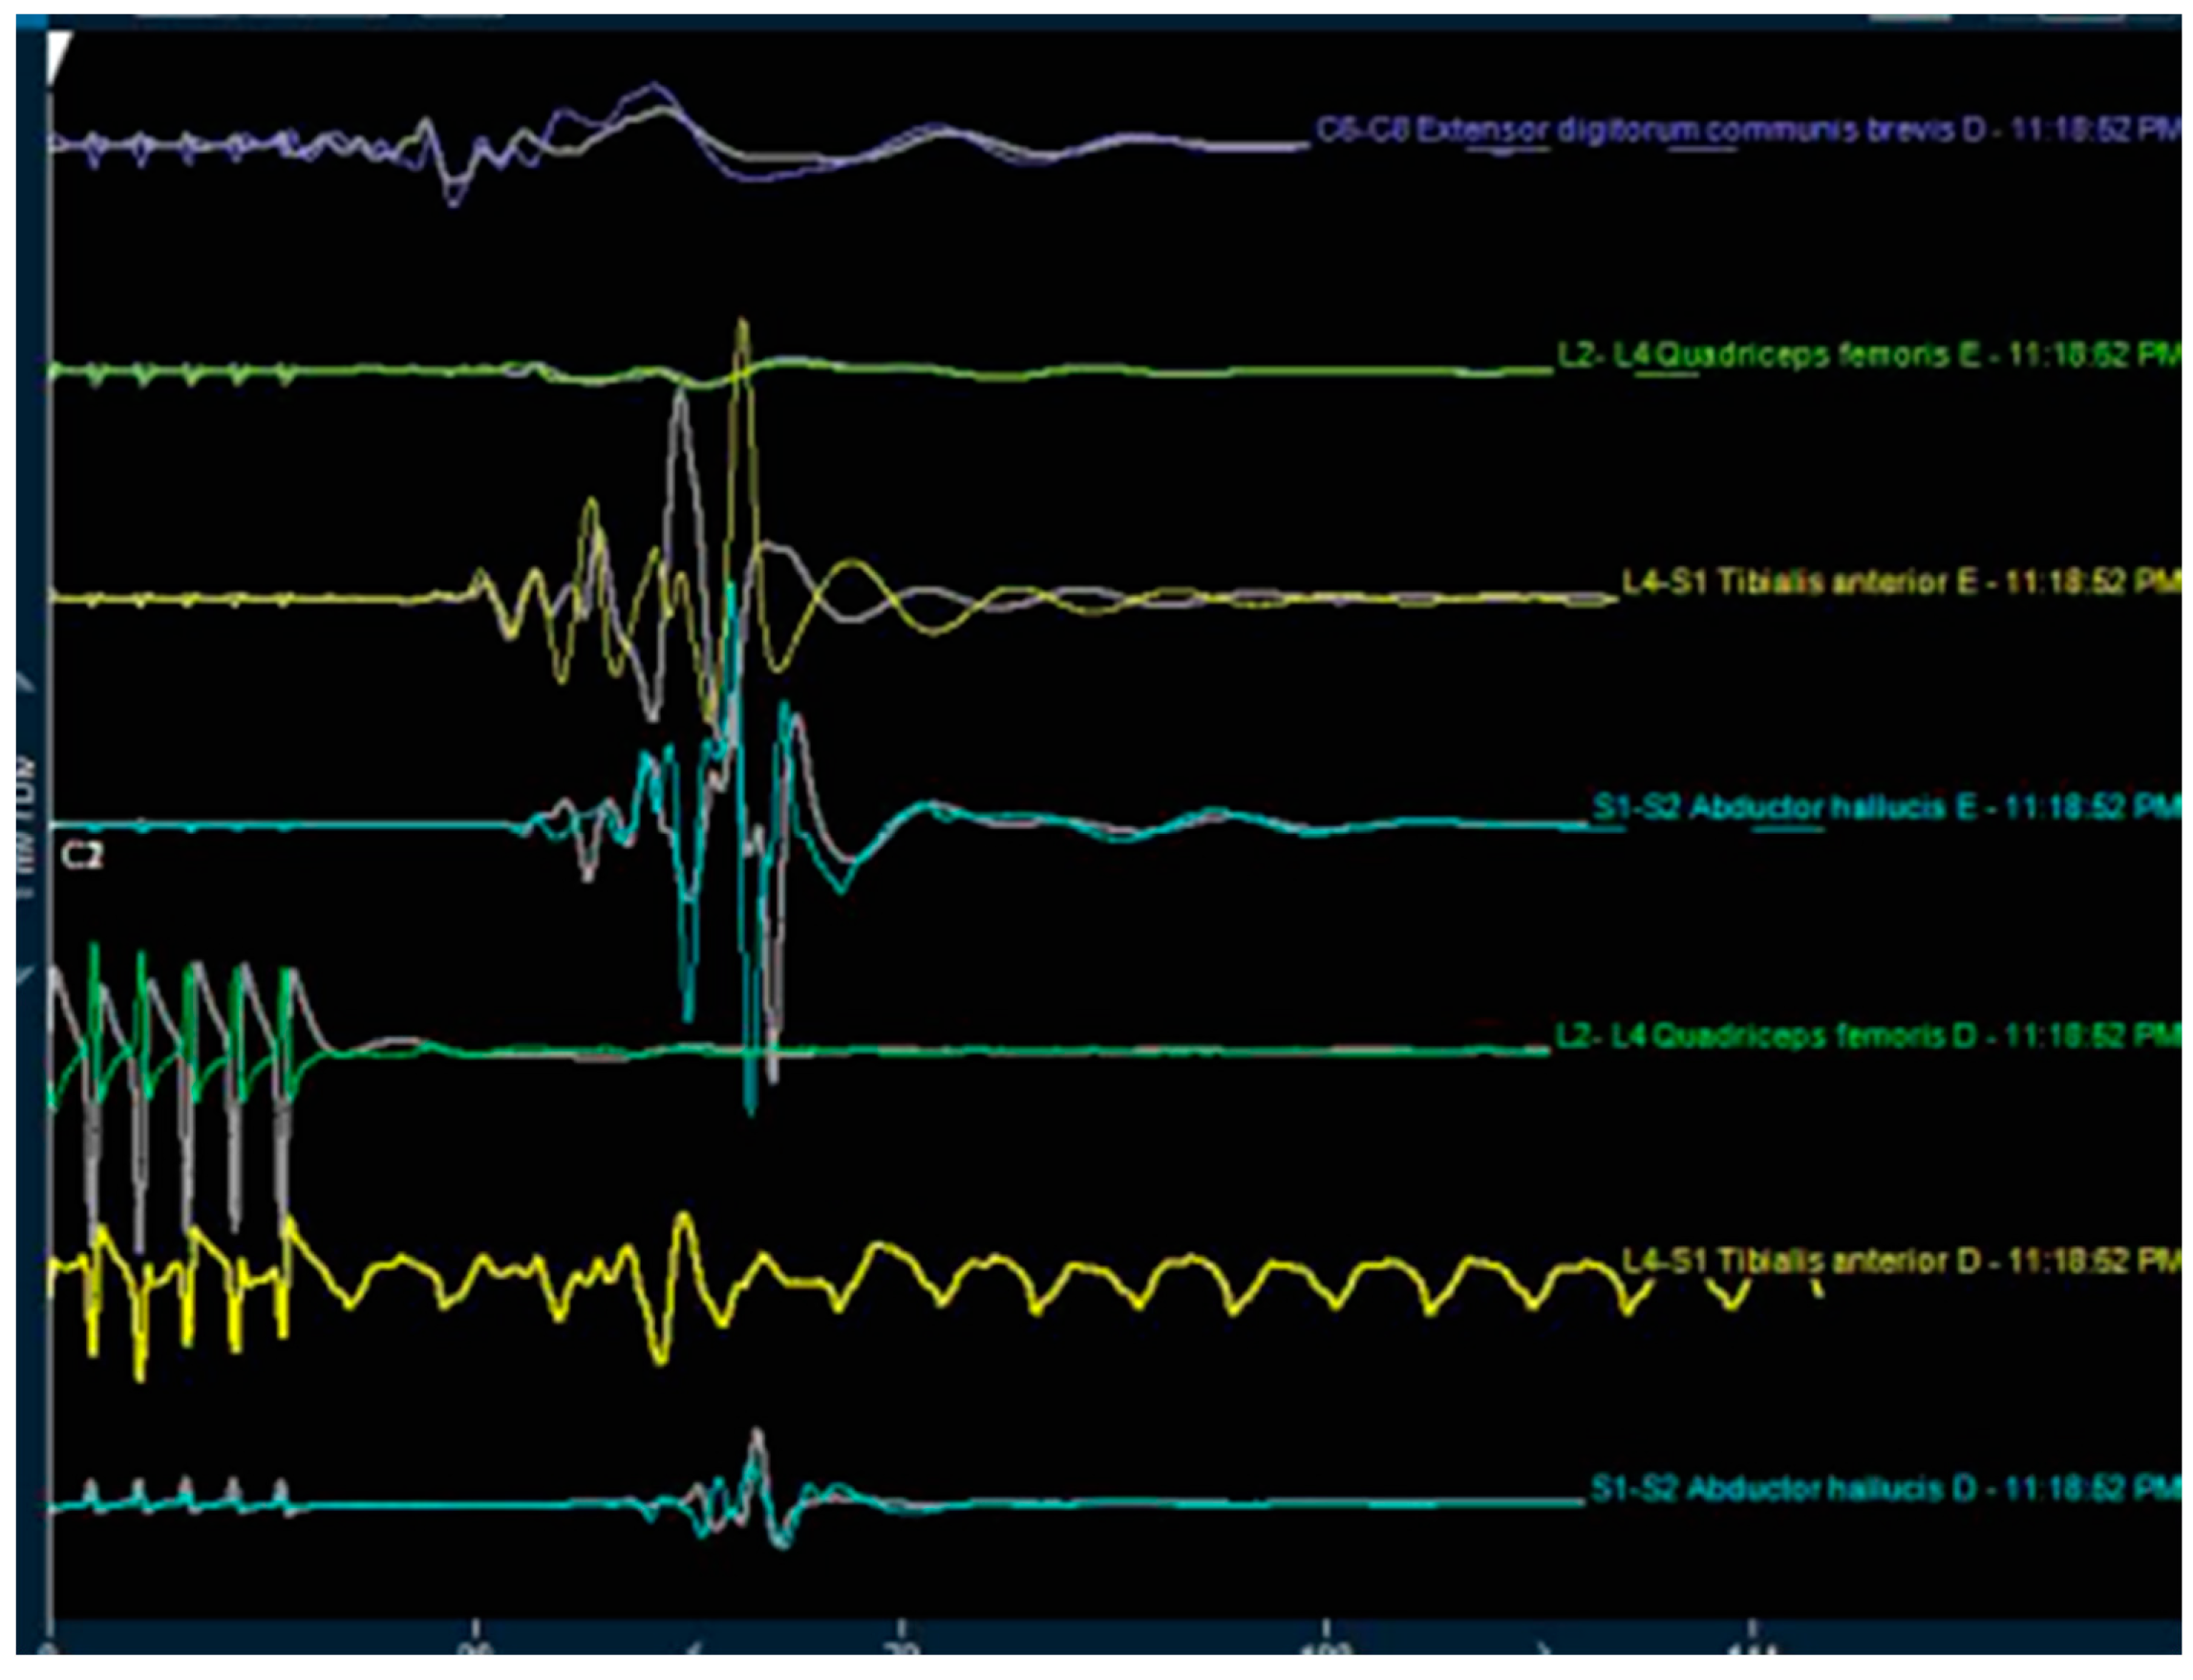

2.4. Anesthesia and Neuromonitoring

| Neuromonitoring Modality | Mean Voltage (MV) | Number of Patients | Standard Deviation | Standard Error Mean | ||||

|---|---|---|---|---|---|---|---|---|

| SSEP Intraoperatively | 11.82 | 33 | 1.845 | 0.321 | ||||

| SSEP Postoperativly | 15.36 | 33 | 1.245 | 0.217 | ||||

| TCMEP Intraoperatively | 10.61 | 33 | 1.413 | 0.246 | ||||

| TCMEP Postoperatively | 17.64 | 33 | 0.962 | 0.168 | ||||

| Mean Voltage | Standard Deviation | Standard Error Mean | 95% Confidence Interval | t | df | Significance (2-tailed) | ||

| Lower | Upper | |||||||

| SSEP MV Intra–SSEP MV Postoperatively | −3.545 | 2.223 | 0.387 | −4.334 | −2.757 | −9.161 | 32 | <0.0001 |

| TCMEP MV intra–TCMEP MV Postoperatively | −7.030 | 1.311 | 0.228 | −7.495 | −6.566 | −30.814 | 32 | <0.0001 |